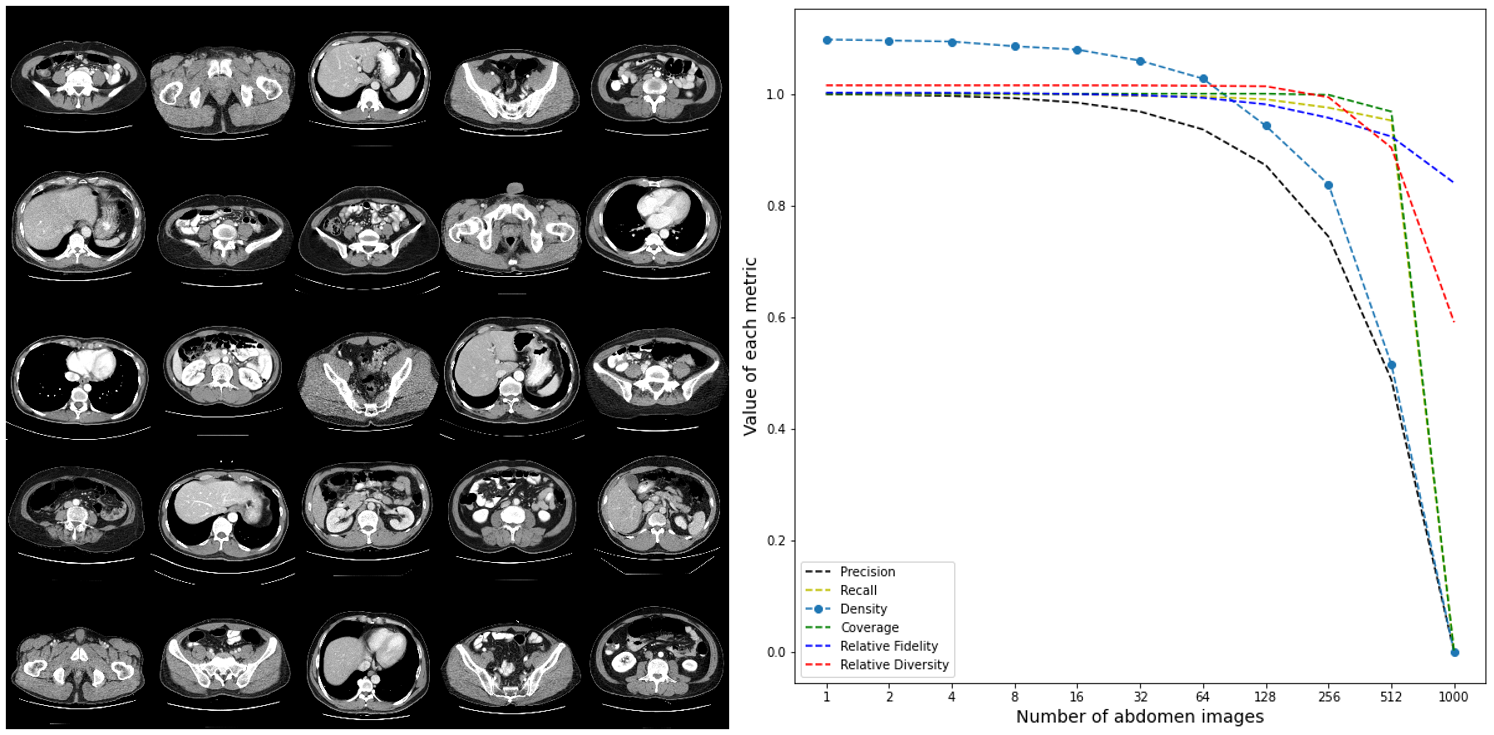

Finally, we had experimented inserting abdomen CT images among brain CT images to observe how metrics act to outliers. This is discussed in Appendix D.

Appendix D Appendix

First, we had sampled 1,000 real brain CT images randomly. Then, for in range to , we replaced brain CT images to abdomen CT images(As we only sampled 1,000 images, was considered as 1,000). The result is shown in Figure (11). As the result shows, metrics such as precision, recall, density, coverage converge to zero as n increases. However, our proposed barcode metrics, which is fidelity and diversity does not converge to zero. This is basically barcode metrics are based on distances, which cannot be zero unless all distances are zeros. More specifically, density and precision are not that robust compare to our metrics.